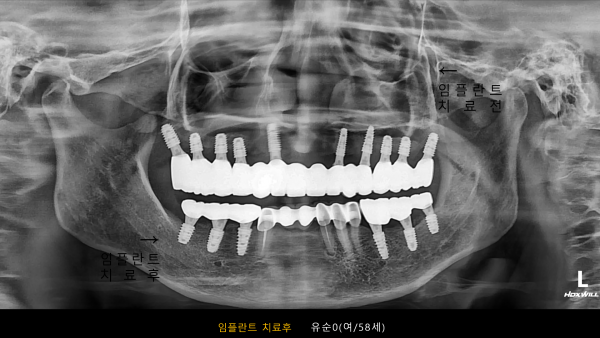

고난도 센터 | 여) 58세